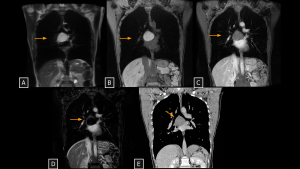

Fig 3: Case 1 – Bronchogenic Cyst:

Panels A–D (MRI) show a cystic lesion located in the subcarinal region (arrows). The T2-weighted image without fat saturation (A) demonstrates typical fluid signal, while the T1-weighted image with fat saturation (B) reveals high signal intensity, indicative of thick or hyperproteinaceous content. Post-contrast (C) and subtraction (D) images confirm the absence of internal enhancement. Panel E (Coronal CT) shows a hypoattenuating lesion in the corresponding subcarinal region.

SYSTEMATIC APPROACH: 1. Age: Variable (Pediatric to Adulthood) | 2. Morphology: Unifocal, well-circumscribed fluid density (0–20 HU) or high attenuation (protein/calcium) | 3. Enhancement: Absent (Avascular) | 4. Anatomical Anchor: Subcarinal or paratracheal (no tracheal communication).